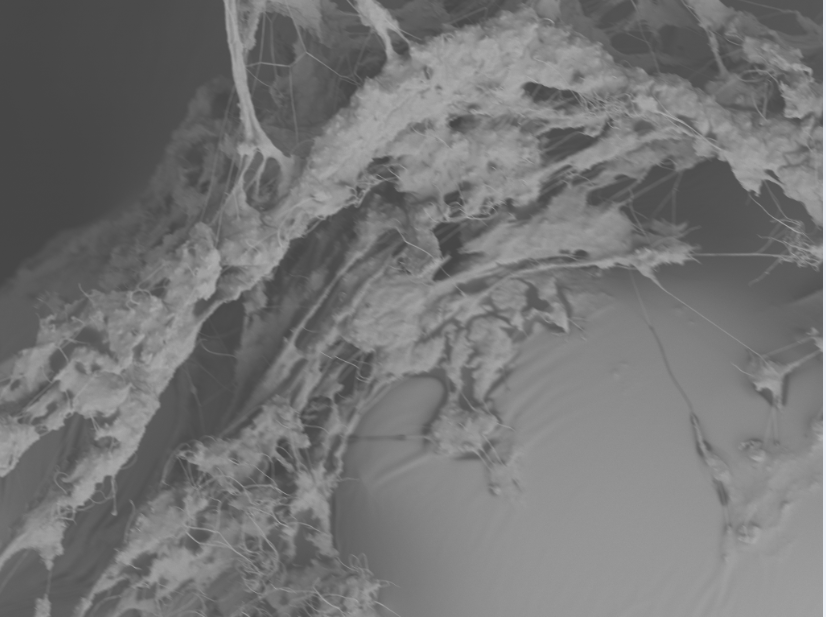

SEM Breast Implant Images

Breast implant surfaces are made of silicone. However, surface texturing is used to increase tissue adhesion and prevent movement following placement.

The deposition of wound-healing proteins on the implant surface facilitates staphylococcal infection.

Incorporation of host collagen into S. epidermidis biofilm

Incorporation of host fibrinogen into S. epidermidis biofilm

Similarly to the urinary catheters, staphylococci, including S. aureus and S. epidermidis, exploit the deposition of wound-healing glycoproteins to bind to the implant surface. Textured breast implant surfaces have increased host glycoprotein deposition and therefore higher bacterial colonization. Staphylococci and Pseudomonas aeruginosa are the primary Gram-positive and Gram-negative cause of breast implant-associated infections. We have developed a mouse model to study the implant-host-pathogen interactions that facilitate infection. Our future studies aim to translate the results from these studies into better surveillance, prevention, and treatment strategies.